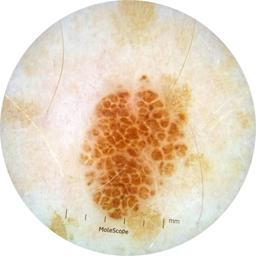

MEL-SELF - Dermoscopic

- Name: MEL-SELF - Dermoscopic

- Number of images: 3,008

- Number of specified lesions: 837

- Number of specified patients: 246

Dermoscopic lesion images (close-up views of benign and malignant lesions) from the MEL-SELF trial (the Melanoma Self Surveillance trial).